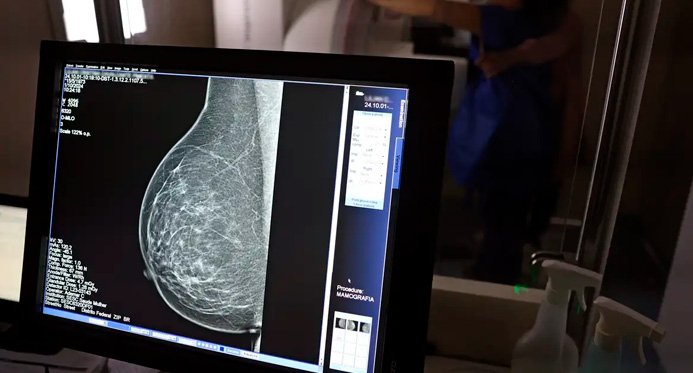

A mamografia é considerada o principal revista da triagem do cancro de peito. Ele permite identificar alterações porquê nódulos, cistos e espessamento do tecido antes dos sinais clínicos. Quando suspeito, a biópsia pode ser indicada para confirmar o diagnóstico.